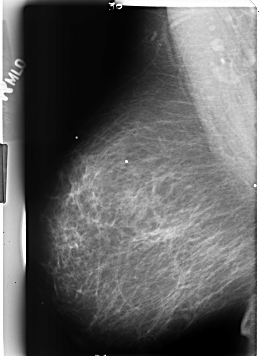

B_3217_1.RIGHT_MLO

RIGHT_MLO LINES 4616 PIXELS_PER_LINE 3360 BITS_PER_PIXEL 12 RESOLUTION 50 NON_OVERLAY